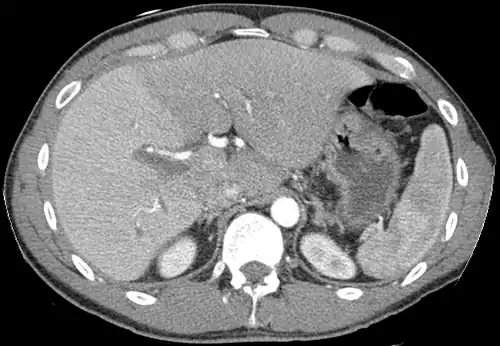

With the recent advances of noninvasive imaging, living liver donors usually have to undergo imaging examinations for liver anatomy to decide if the anatomy is feasible for donation. The evaluation is usually performed by multidetector row computed tomography (MDCT) and magnetic resonance imaging (MRI). MDCT is good in vascular anatomy and volumetry. MRI is used for biliary tree anatomy. Donors with very unusual vascular anatomy, which makes them unsuitable for donation, could be screened out to avoid unnecessary operations.

-

MDCT image. Arterial anatomy contraindicated for liver donation -

MDCT image. Portal venous anatomy contraindicated for liver donation -

MDCT image. 3D image created by MDCT can clearly visualize the liver, measure the liver volume, and plan the dissection plane to facilitate the liver transplantation procedure. -

Phase contrast CT image. Contrast is perfusing the right liver but not the left due to a left portal vein thrombus.